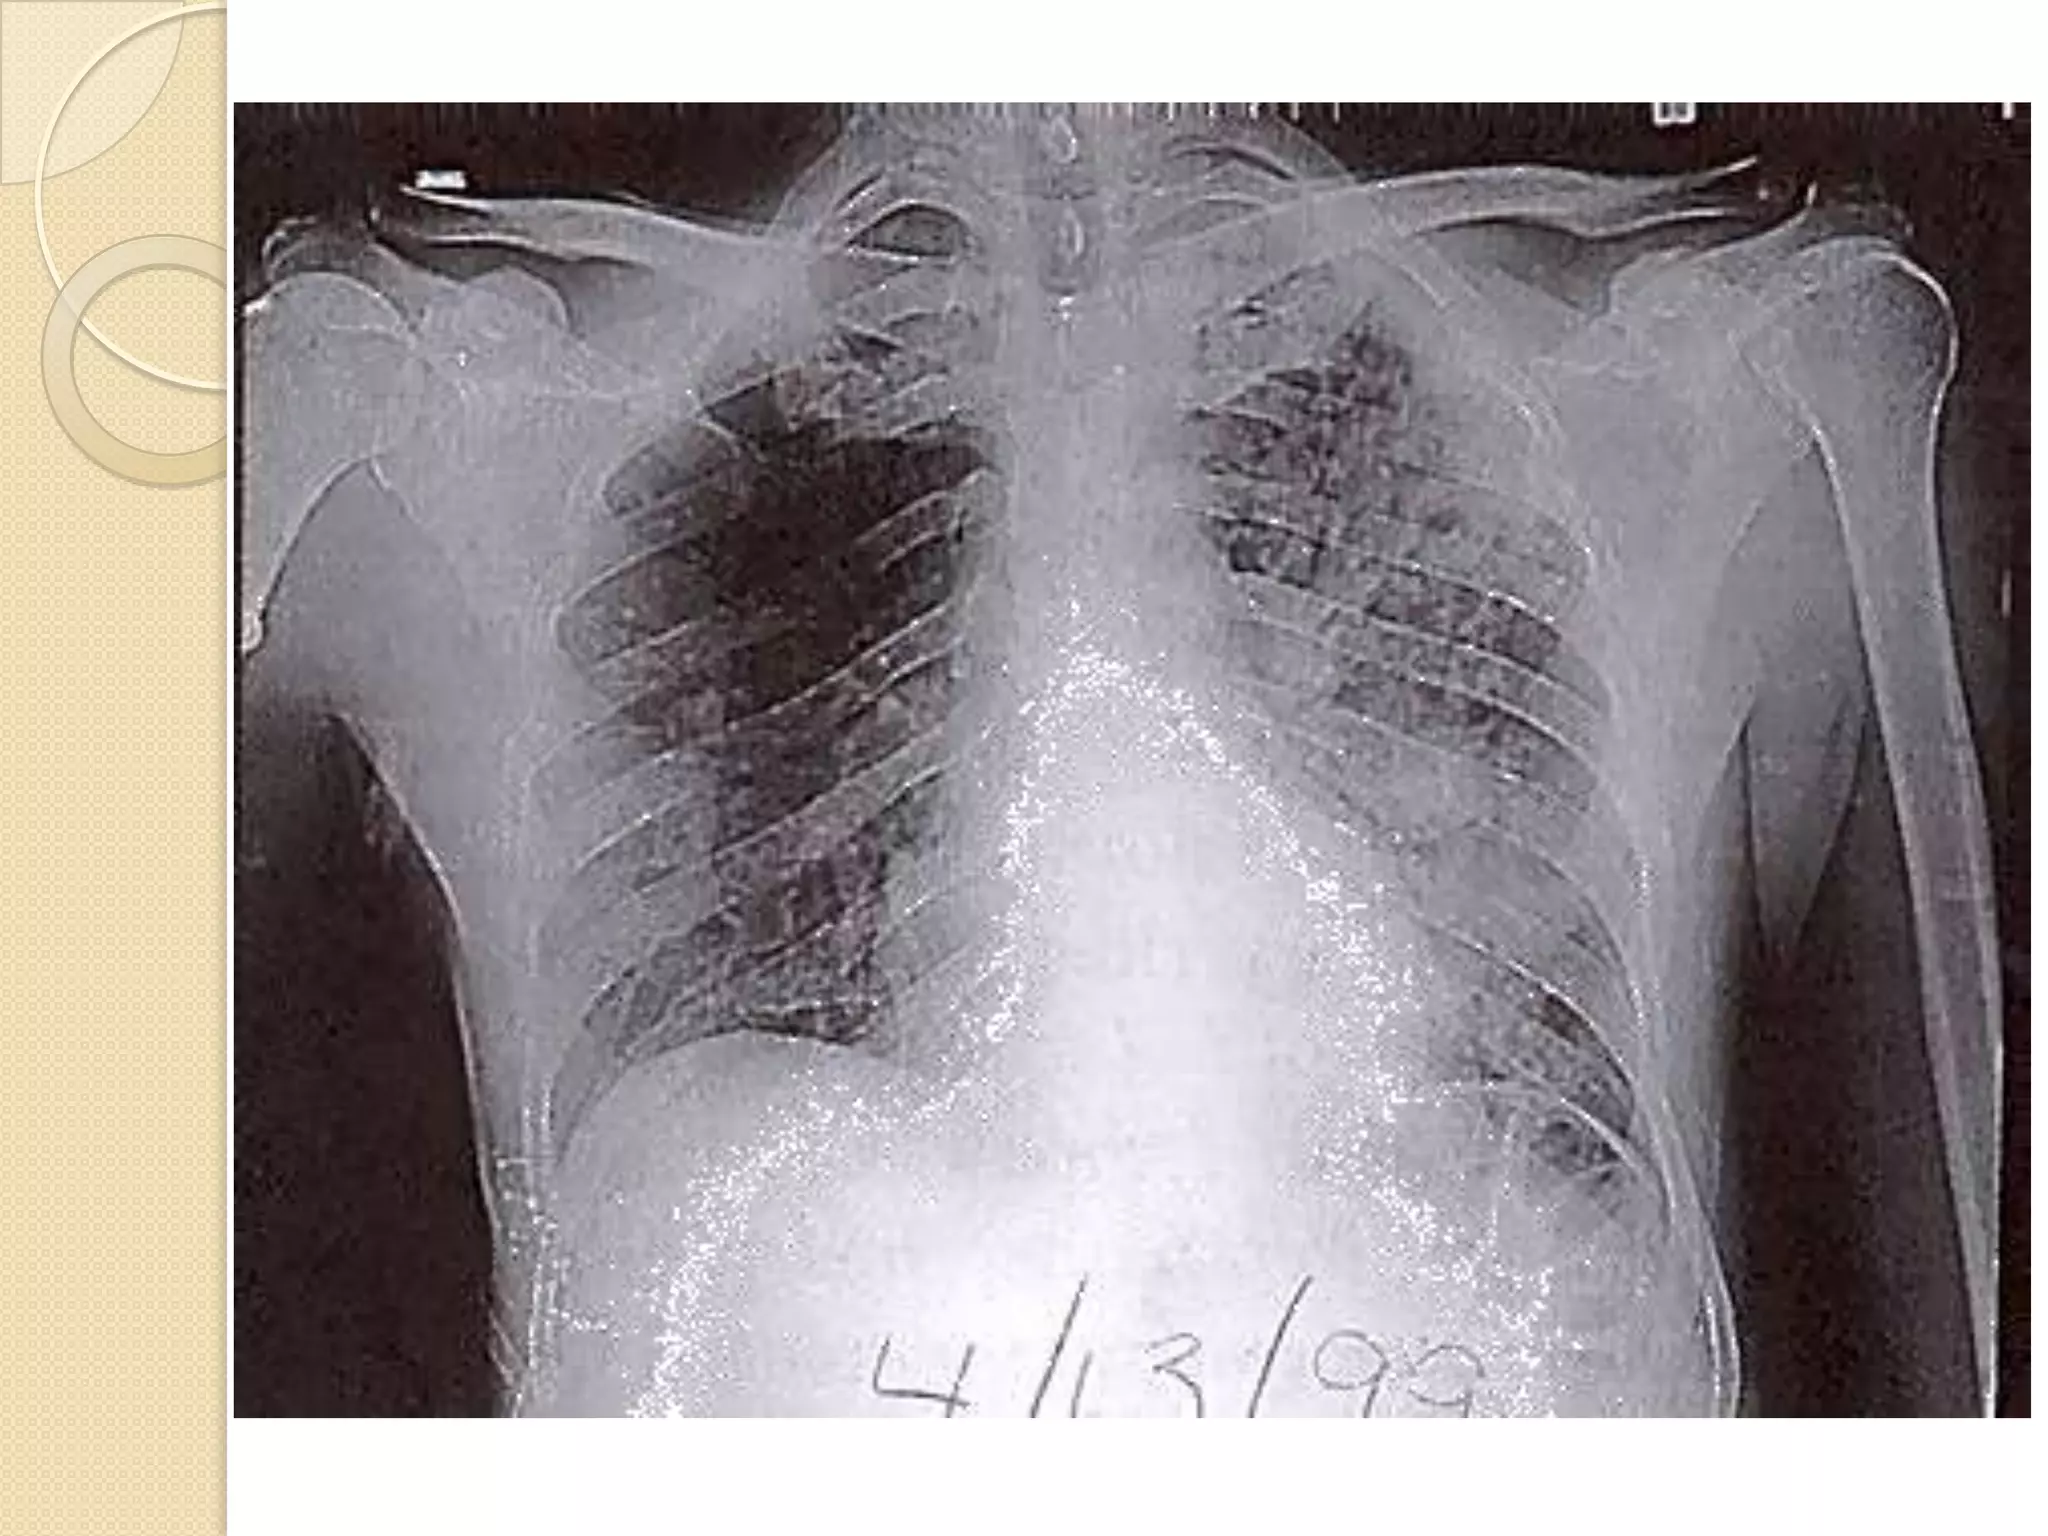

Diagnosis

 Positive PPD

 Chest X-Ray

 Microscopy and culture – it is sensitive